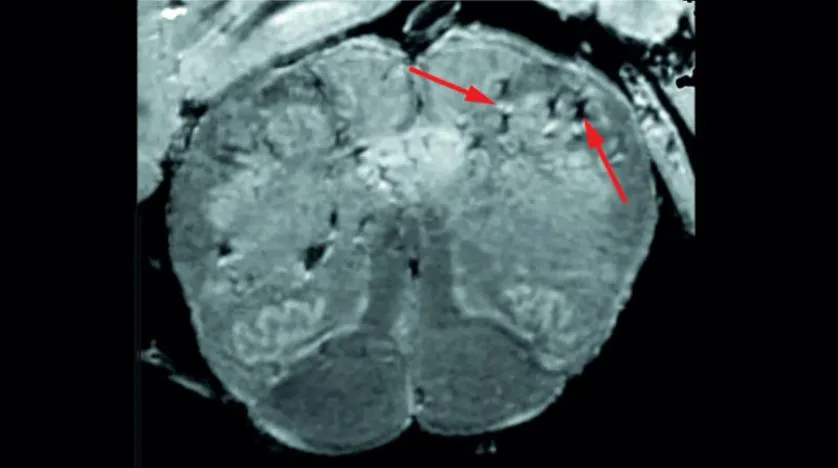

Araştırmacılar beyindeki kan damarlarında hasar belirtileri buldular (ABD Ulusal Sağlık Enstitüsü)

Başlangıç olarak, araştırmacılar vakaların, Kovid-19’a karşı son derece savunmasız olduğuna inandıkları koku almayı sağlayan bölge “Olfactory bulb”larını ve beyin saplarını incelemek için çoğu MRI’dan (Manyetik Rezonans Görüntüleme cihazı) 4 ila 10 kat daha hassas olan özel bir yüksek güçlü cihaz kullandılar.

Olfactory bulb koku alma duyumuzu kontrol ederken, beyin sapı nefesimizi ve kalp atış hızımızı kontrol ediyor. Yapılan taramalar, her iki bölgede de, genellikle iltihaplanmaya işaret eden hiperintens adı verilen çok sayıda parlak nokta olduğunu ve hiperestezi adı verilen kanama olduğunu gösteren koyu lekelerin olduğunu ortaya çıkardı.

Araştırmacılar daha sonra bu taramaları, MRI’da görülen noktaları mikroskop altında yakından incelemek için bir kılavuz olarak kullandılar. MRI’daki parlak noktaların normalden daha ince kan damarları içerdiğini ve bazen fibrinojen gibi bazı proteinleri beyne sızdırdığını, bunun da bir bağışıklık reaksiyonunu tetiklenmesine sebep olabileceğini saptadılar. Bu nokta, mikroglia adı verilen beynin kan ve bağışıklık hücrelerinden gelen T hücreleri ile çevriliyken koyu noktalar, pıhtılaşmış ve sızdıran ancak bağışıklık tepkisi olmayan kan damarlarını içeriyordu.